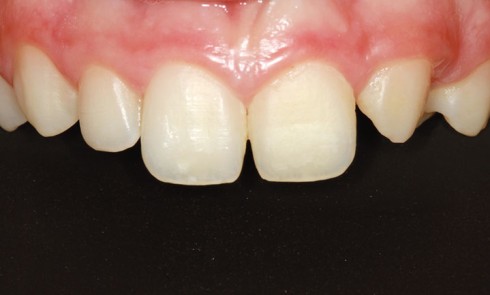

Article réservé à nos abonnés Agénésie des incisives latérales maxillaires : traitement par ouverture des espaces

Le cas présenté ici a été traité en orthodontie linguale. Il montre la nécessité d’interventions pluridisciplinaires préméditées afin d’obtenir un...